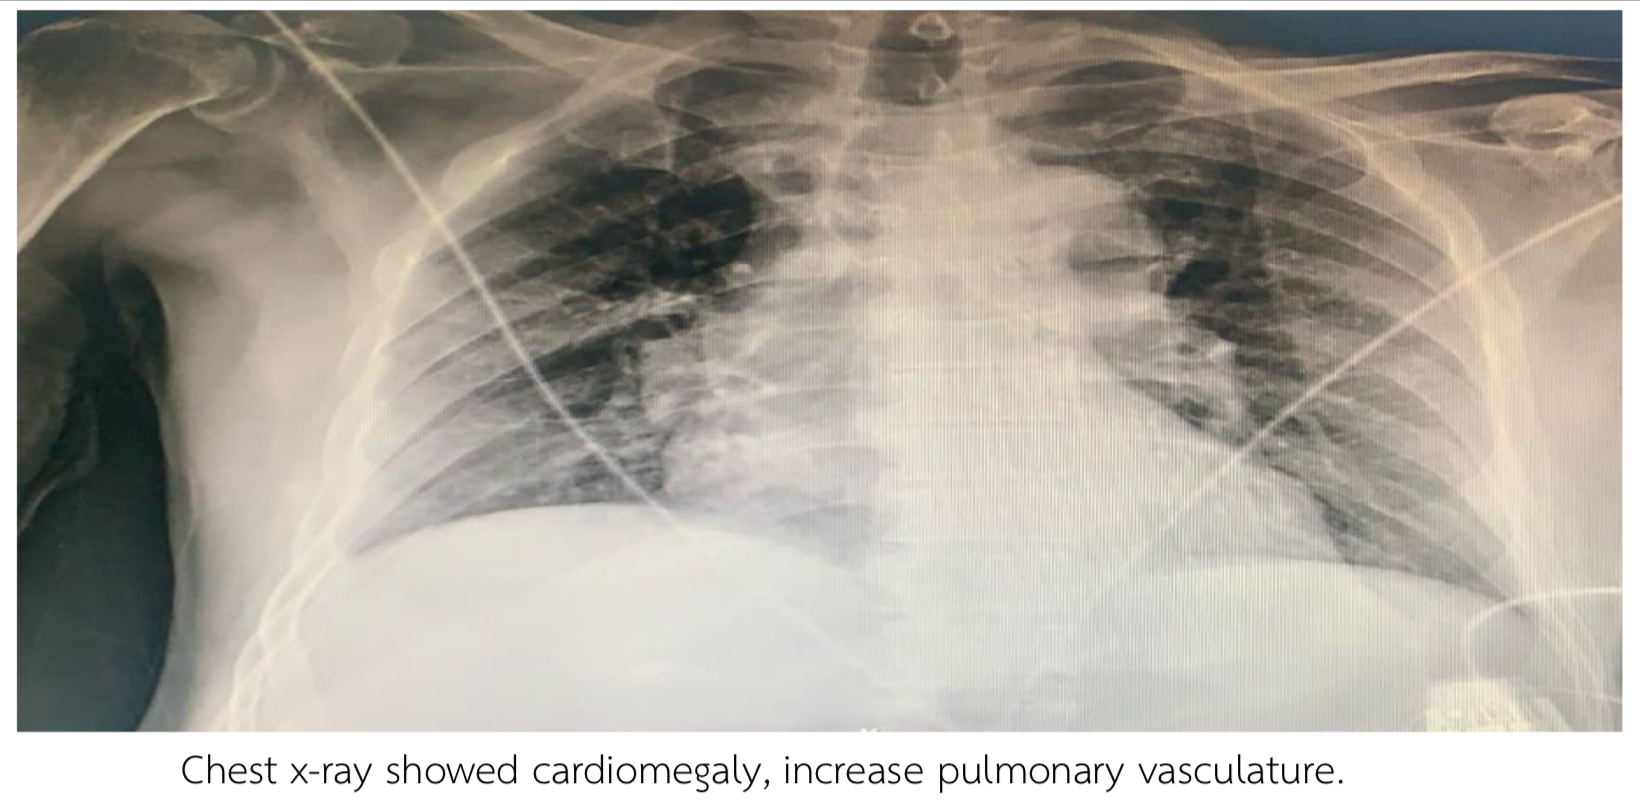

Thai male 69 years, Risk Hypertension, Dyslipidemia presented with chest pain 2 hours prior to admission. Blood pressure 104/62 mmHg Heart rate 76 bpm. Heart regular, fine crepitation both lower lungs. EKG showed Normal sinus rhythm, 84 bpm, ST elevation II, III, AVF, diffused ST depression V2-V6. Echocardiogram showed LVEF 42%, Global wall Hypokinesia, no significant valvular heart disease. Troponin T was positive 10,400 pg/ml. Chest x-ray showed cardiomegaly, increase pulmonary vasculature

EKG showed Normal sinus rhythm, 84 bpm, ST elevation II, III, AVF, diffused ST depression V2-V6. Echocardiogram showed LVEF 42%, Global wall Hypokinesia, no significant valvular heart disease. Troponin T was positive 10,400 pg/ml. Chest x-ray showed cardiomegaly, increase pulmonary vasculature.